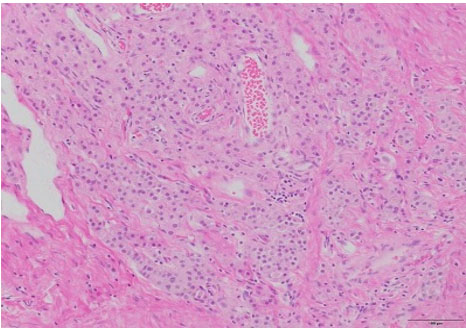

Surgical pathology revealed a 3.0 × 3.0 × 2.2 cm soft, pale-tan lobulated mass within the left testis (Figure 1). Histology demonstrated pure seminoma with concomitant Leydig cell hyperplasia and no other non-seminomatous germ cell components (Figure 2). The seminoma displayed the classic morphology of epithelioid tumor cells with clear cytoplasm, boxed-off nuclei, and fibrous bands with associated lymphocytes (Figure 3). Immunohistochemistry was not required for the diagnosis. Initial tumor markers (beta-HCG, LDH, and AFP) were normal.

Figure 2: Leydig cell hyperplasia, H&E, 200×.

Figure 3: Seminoma, H&E 400×.